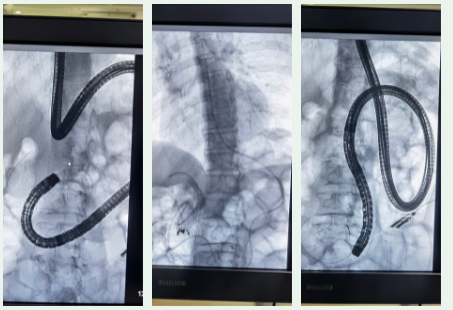

手术当天,消化内科郭锐主任及李娟医师、张磊护师结合患者具体情况,进行了手术。术中由于患者的消化道解剖结构已经改变,对输入袢的识别以及接近胆管开口的过程具有较高的挑战性,随时有黏膜撕裂或穿孔的可能。郭锐主任及李娟医师凭借着丰富的内镜操作经验以及夯实的理论基础,经过1个小时的努力,在重重迷路中应变,成功完成十二指肠乳头插管,括约肌切开术、乳头开口球囊扩张术、网篮取石,置入鼻胆引流管等操作。手术顺利,术后患者恢复良好,未发生并发症,现患者已好转出院。

“目前针对消化道重建后的胆总管结石患者,临床上主要以外科手术与ERCP取石术两种治疗手段;ERCP具有微创的独特优势,患者免受外科创伤,术后迅速恢复,不影响生活质量。对于无法耐受手术的患者而言无疑是“救命稻草”。但消化道手术往往需要破坏正常消化道结构后进行消化道重建,这位患者既往患有胃癌手术史,导致ERCP进镜路径的改变和正确进镜路径辨识的困难。目前,我国ERCP诊治指南将消化道重建的ERCP操作归属为IV级难度的ERCP手术。并且,胃癌术后腹腔粘连也为实施内镜下操作增加了难度,对医师的理论水平和操作技术有极高的要求。”

据了解,常规ERCP操作过程中,一般情况下,将内镜从患者口中探入,内镜顺着患者的食管、胃到达十二指肠很容易寻找到乳头开口,经十二指肠乳头插管后,才能进行胆管取石治疗。十二指肠插管成功是手术的基础。

目前,我国三级医院的内镜医生常规十二指肠乳头插管成功率高达95%以上。然而,消化道重建ERCP插管成功率仅仅为68%,即便是经验丰富的内镜专家,插管失败率也达到20%。因为,消化道重建的方式不同,例如结肠前吻合造成输入襻较长,常规内镜无法到达十二指肠乳头开口,为内镜下寻找十二指肠乳头造成不同程度的困难;而且,消化道重建的十二指肠乳头插管与常规乳头插管方式完全相反,也为操作带来一定困难。